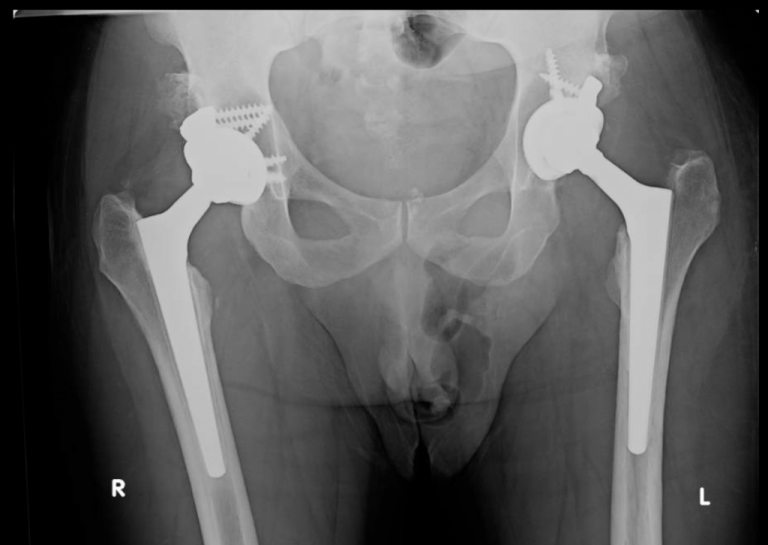

Bilateral Hip Dysplasia When To Preserve, And When To, 52 OFF Is There A Cure For Hip Dysplasia In Humans Osteotomy is surgery to realign. Hip dysplasia is the medical term for a hip socket that doesn't fully cover the ball portion of the upper thighbone. Several surgical techniques can be used to correct hip dysplasia while preserving the existing hip joint. Medications and cortisone injections can decrease the inflammatory component of. One of the more common is a. Mayo. Is There A Cure For Hip Dysplasia In Humans.

Severe Hip Dysplasia THA Darwin Chen, MD Is There A Cure For Hip Dysplasia In Humans Mayo clinic hip dysplasia surgeons are at the forefront of new and innovative treatment options for patients with hip dysplasia. Mayo clinic has extensive experience with. Hip dysplasia is the medical term for a hip socket that doesn't fully cover the ball portion of the upper thighbone. Treatment for hip dysplasia depends on the severity of the condition and when. Is There A Cure For Hip Dysplasia In Humans.